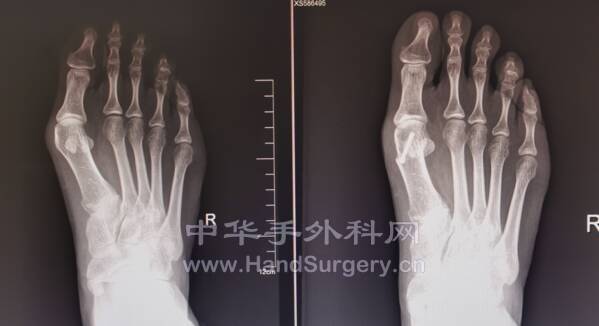

邻居小姐姐,双足拇外翻术后半年

效果满意

mmexport1635523314059.png

mmexport1635523318858.png

mmexport1635523347527.png

mmexport1635523353236.png

再过半年会更好看!